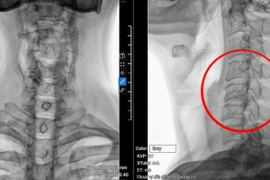

Thoát vị đĩa đệm cột sống thắt lưng có thể gây teo cơ, bại liệt,... Phẫu thuật thoát vị đĩa đệm là một trong những phương pháp điều trị giúp kiểm soát hữu hiệu căn bệnh này.

Thoát vị đĩa đệm đang có xu hướng trẻ hóa, có thể khiến một người khỏe mạnh bị tàn phế suốt đời. Phẫu thuật giải phóng chèn ép là phương pháp giải quyết triệt để tình trạng bệnh lý này.